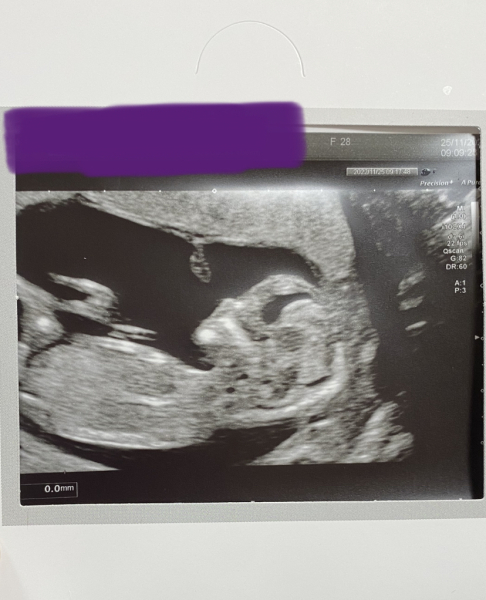

My scan this morning went perfectly and I need not have worried about the previous small measurements. Everything looked great and baby is now measuring slightly ahead of what I thought at 12+6! 🥰😍🤩

Thank you all for the kind messages 🥰 Feeling very relieved and happy! Was incredible seeing how much baby has grown from the initial 6 weeks and then 9 week scan 😍